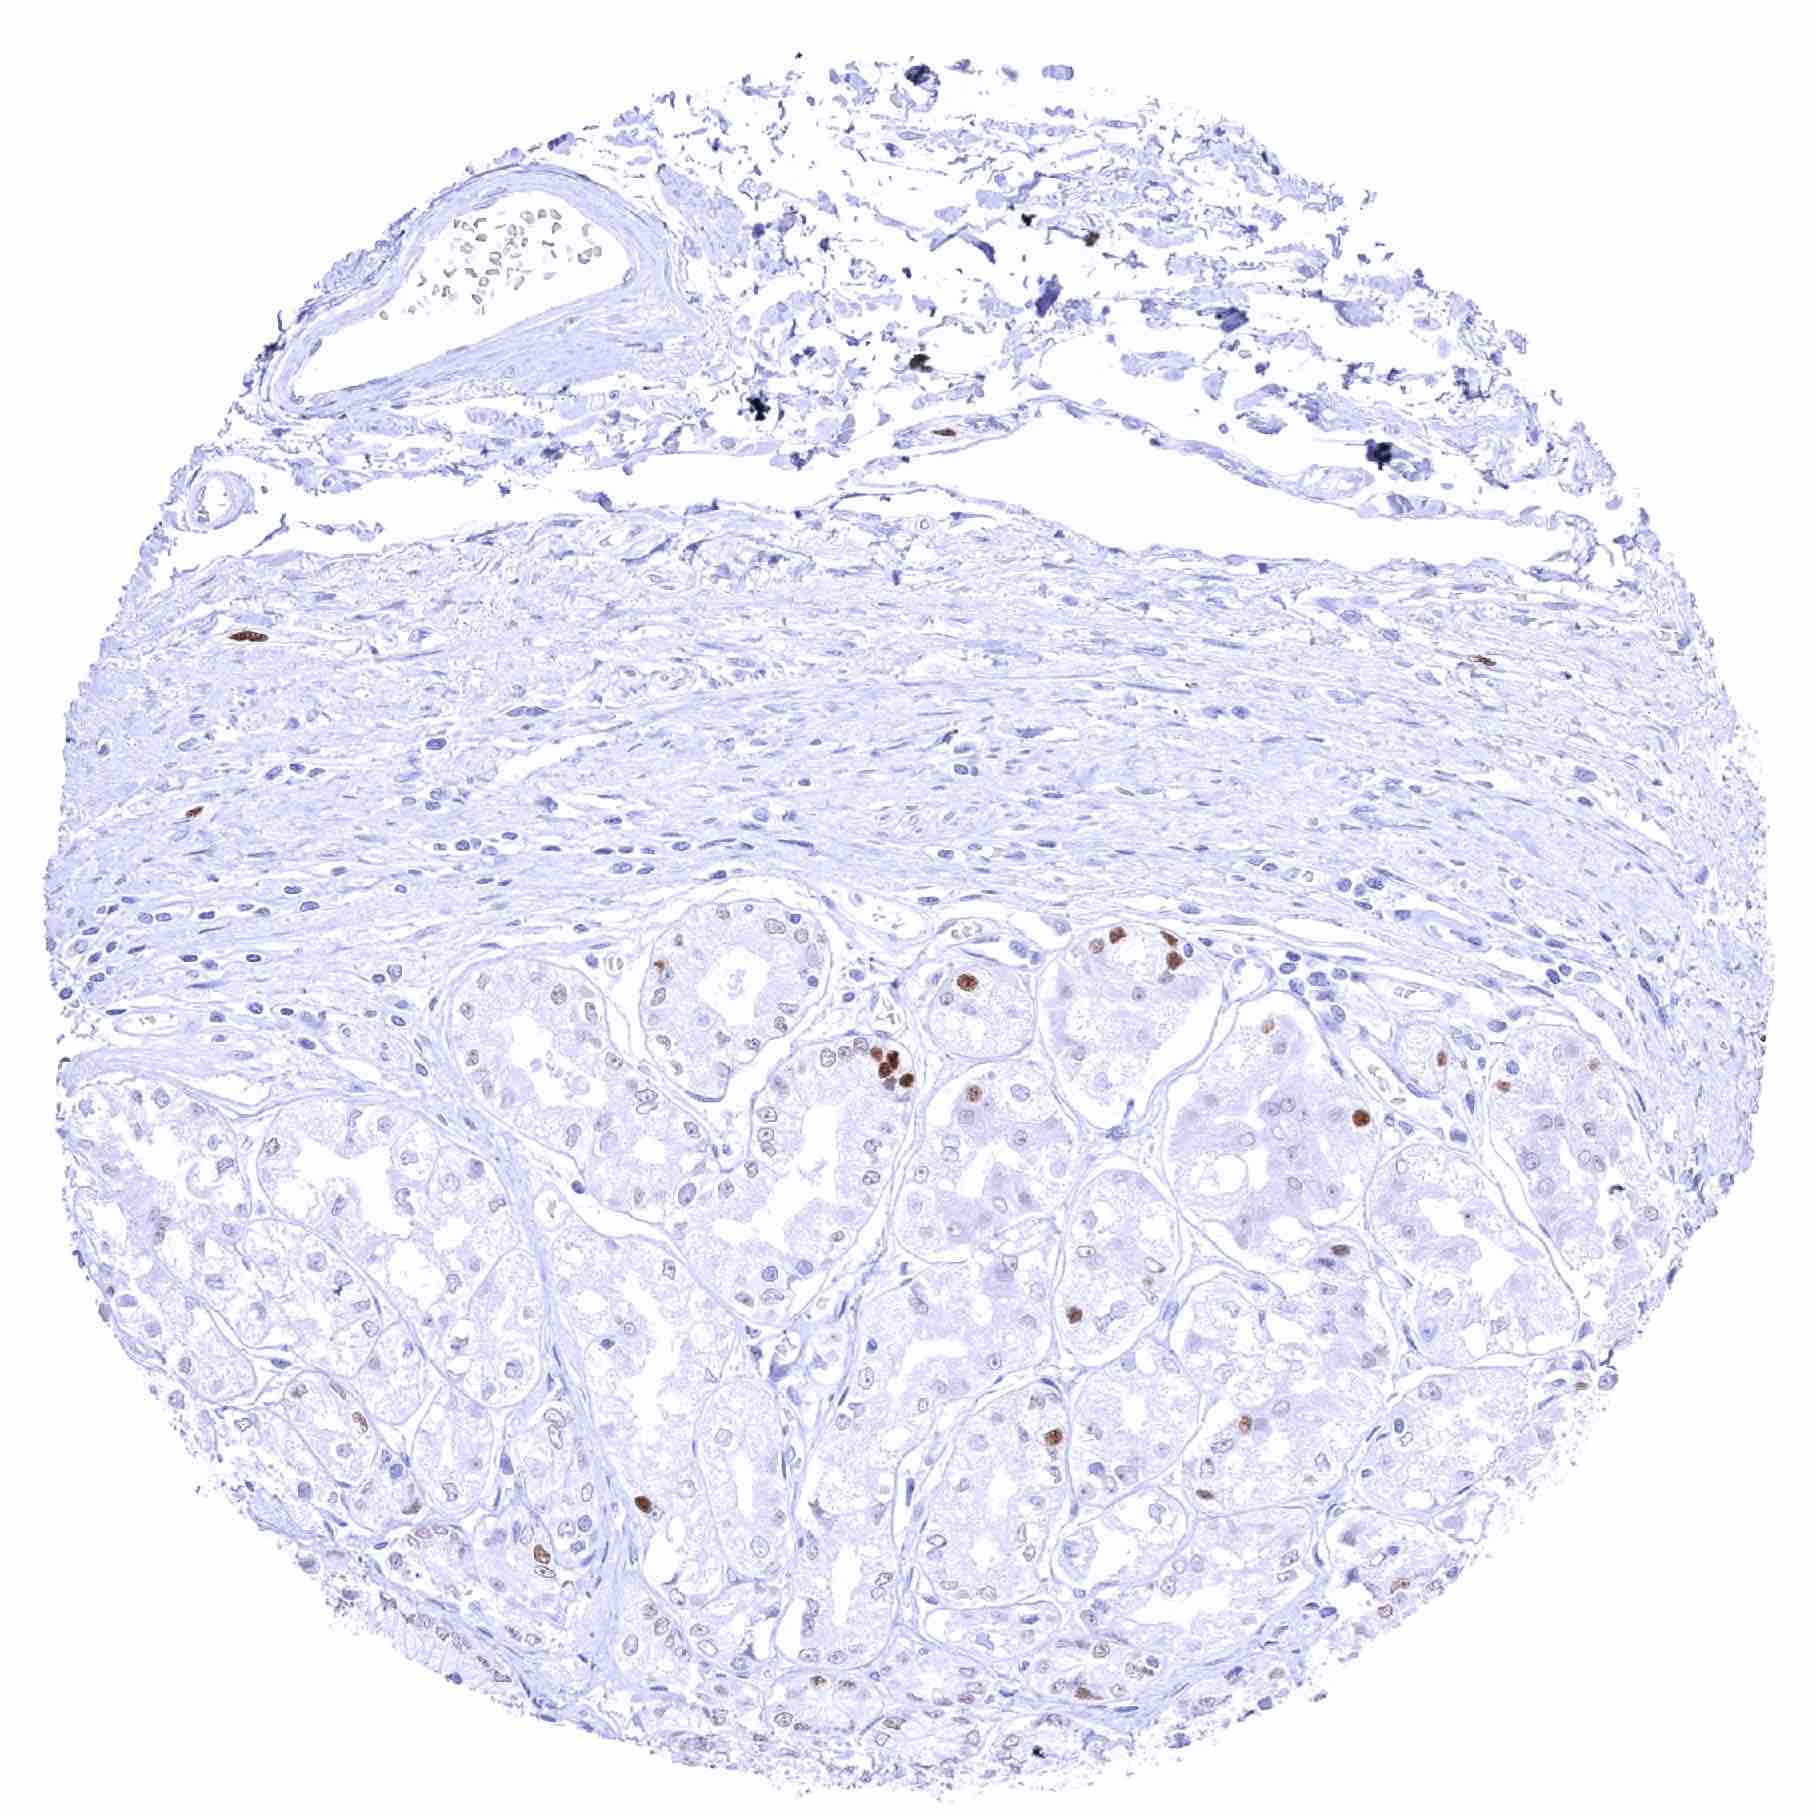

Prostate – Strong SOX2 positivity of a fraction of basal cells